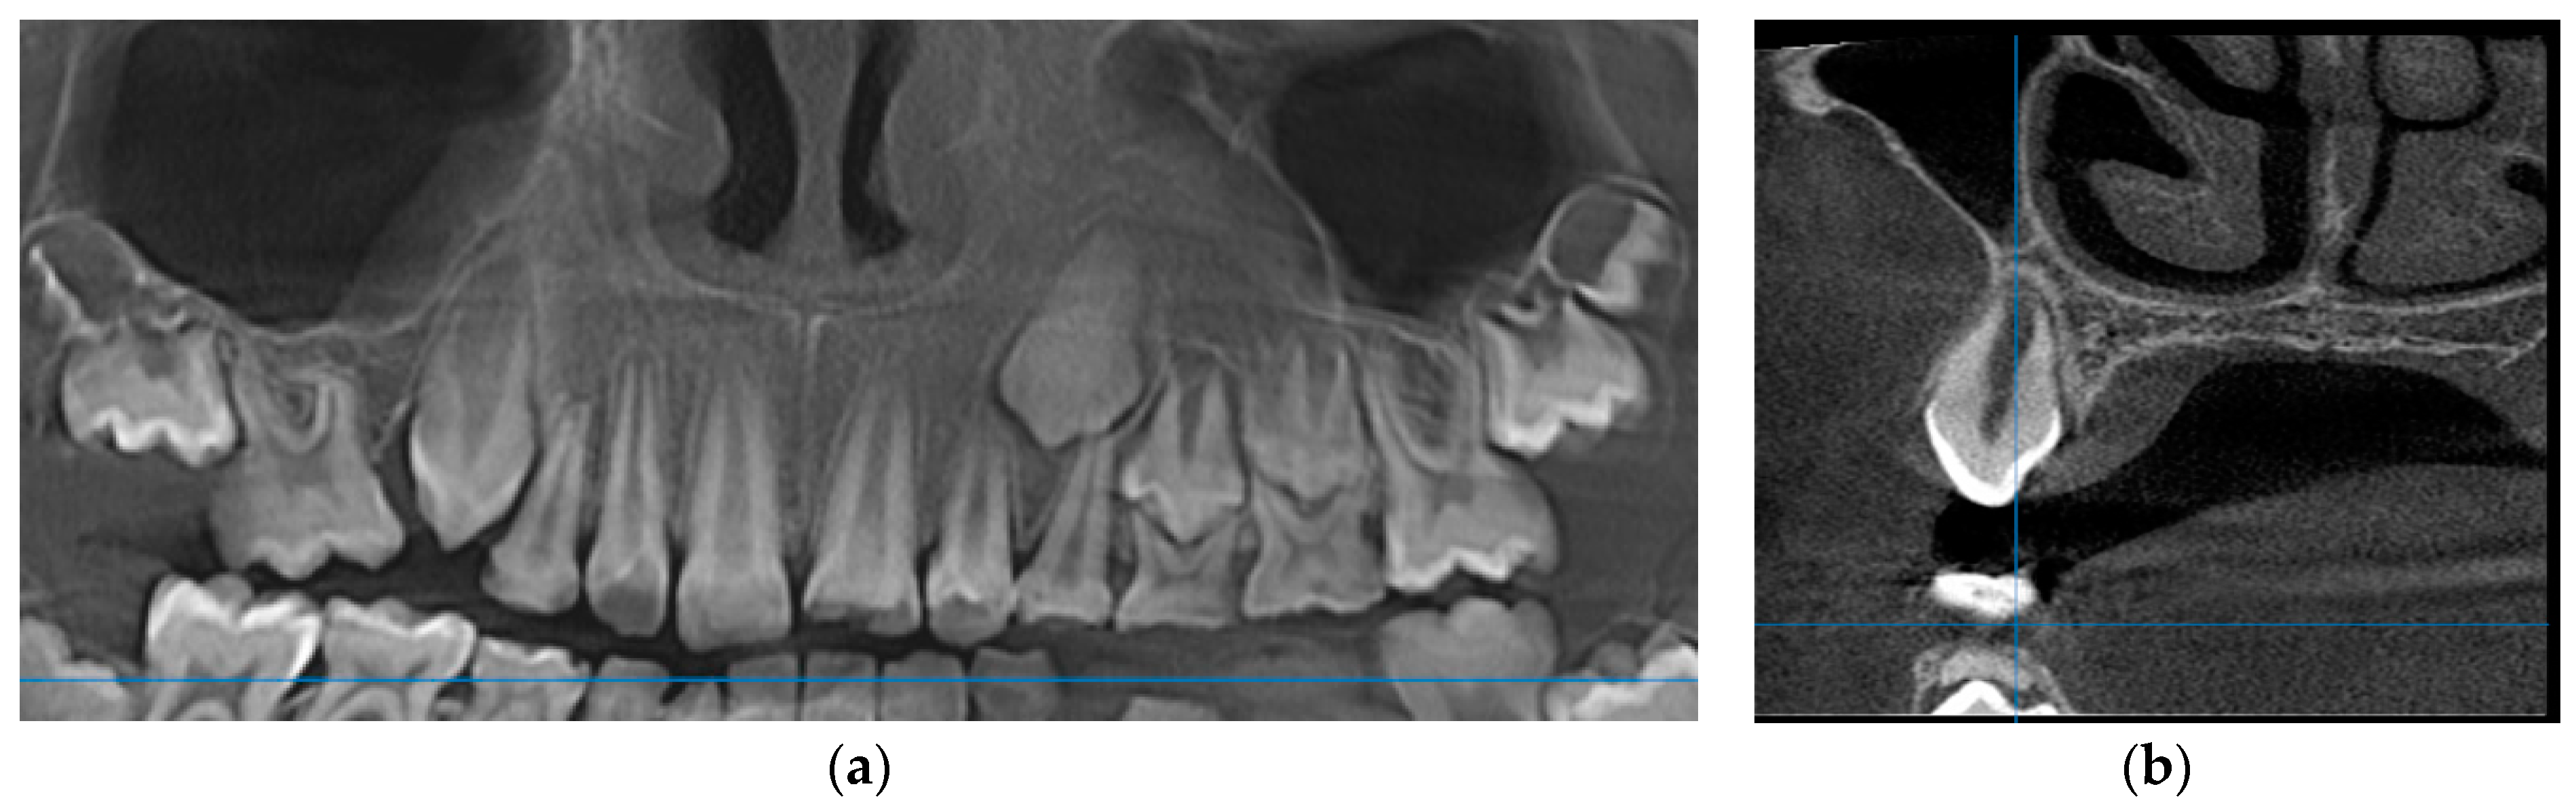

2.2.2. Case 2